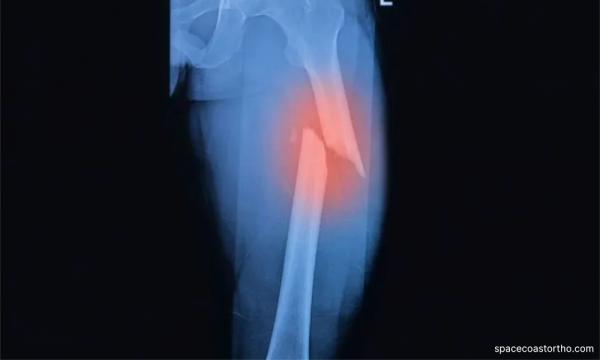

Tendang patah paha budak, pengasuh dipenjara 5 tahun